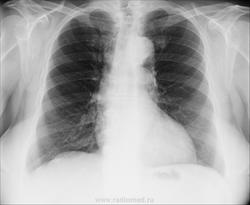

Левый корень не вполне рентгеновская норма, если учитывать, что основу тени корня представляют сосуды. Т.е расширение сосудов, скорее ЛА, может быть вполне.

Да нет, нормальный корень, на мой взгляд.

левый корень б/о

Патологических изменений не нахожу. Не мучила бы ни пациента, ни себя.

Норма

Я не к дообследованию - упаси боже! Я к обьяснению почему так выглядит корень + возраст.